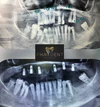

علاج الزرع السني